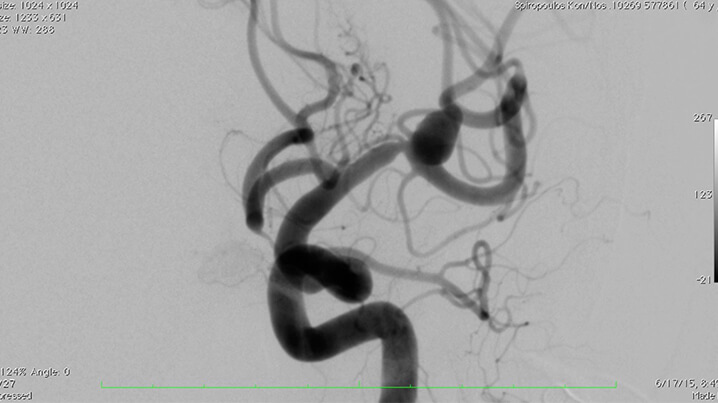

Ο εμβολισμός (ενδαγγειακή θεραπεία) είναι η πλέον αποδεκτή μέθοδος αντιμετώπισης των ενδοκρανίων ανευρυσμάτων.

Tεχνικά, χρησιμοποιούνται ηλεκτρολυτικά αποσπώμενα σπειράματα (GDC-coils) γιά την πλήρωση του ανευρύσματος, που προάγουν την μόνιμη θρόμβωση του ανευρυσματικού σάκκου.

H επέμβαση γίνεται υπό γενική αναισθησία. Mετά τη μηριαία παρακέντηση και την τοποθέτηση ενός ενδοαρτηριακού θηκαριού στην κοινή μηριαία αρτηρία, προωθούμε και τοποθετούμε οδηγό καθετήρα 6F εκλεκτικά στην αρτηρία όπου βρίσκεται το ανεύρυσμα (έσω καρωτίδα η σπονδυλική), με σύστημα συνεχούς εκπλύσεως.

Χρησιμοποιώντας ειδικό μικροκαθετήρα, μέσα από τον οδηγό καθετήρα, καθετηριάζουμε υπερεκλεκτικά τον σάκκο του ανευρύσματος. Στην συνέχεια μέσα από τον μικροκαθετήρα, προωθούμε υπό ακτινοσκοπικό έλεγχο τα μεταλλικά σπειράματα από πλατίνα (coils).